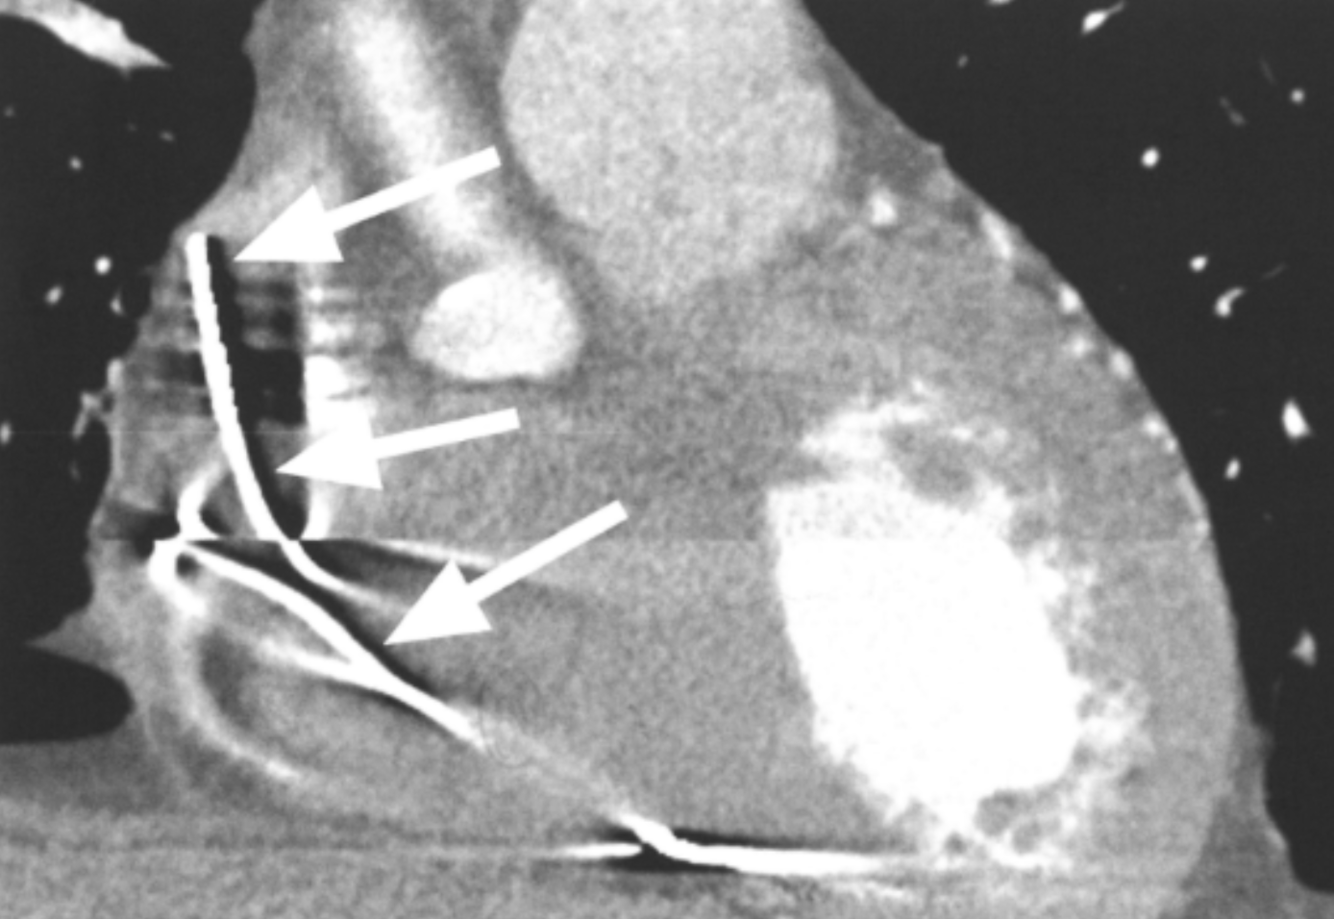

Based on the comparative appearance of these two images, what element of the reconstruction was modified during the second reconstruction?

Slice Thickness

Describe why slice thickness is so important in regards to coronary imaging